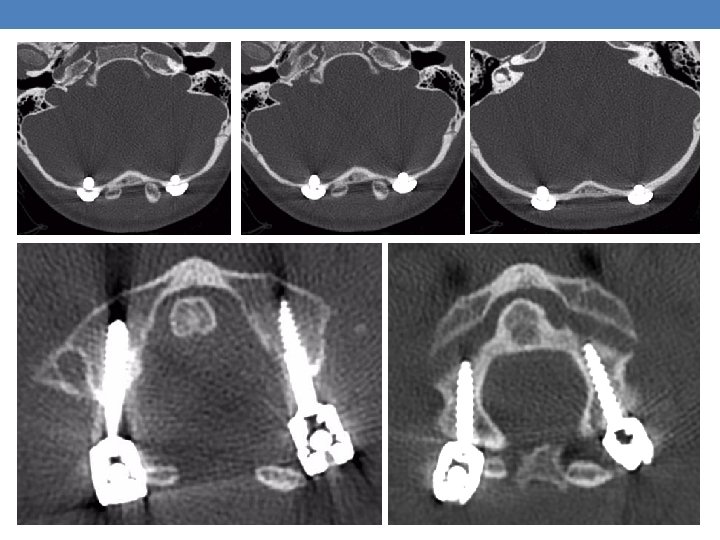

Case 1 A 6 -year-old female with no prior medical history was brought to the emergency room after a high energy car accident, complaining: • Paraplegia • Weakness (0/5) of the right upper limb • Severe neck pain • Respiratory distress The imaging showed an Atlanto-Occipital Dissociation

C 1, C 2 fixation with Goel. Harms technique and C 4 transarticular screw insertion